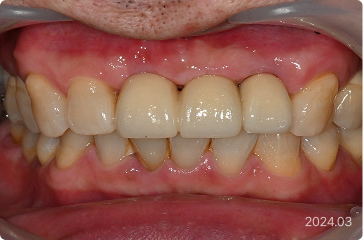

61세, 남 ㅣ해외 출장·짧은 일정

“잦은 해외 출장 때문에 내원해서 치료할 시간이 부족해요.”

치료 전

원데이 임플란트

치료 후

• 해외 출장이 잦아 짧은 체류로 치료 시간 제한

• 의식하진정(수면마취)하 발치 후

8개 임플란트 식립, 다음날 예비 치아 장착

• 발치 , 임플란트 식립 > 최종 보철

약 2개월 내 완성